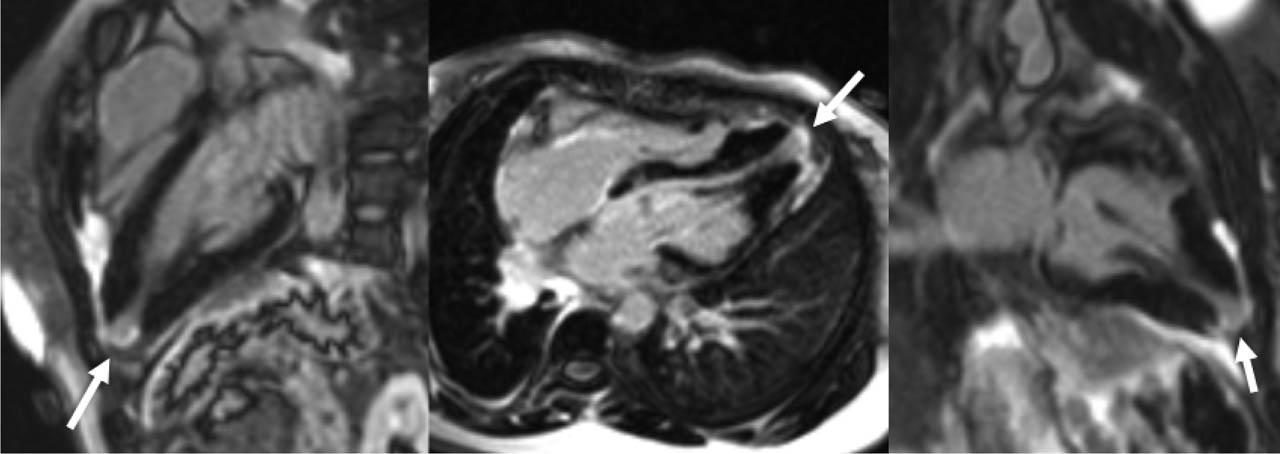

Figure 7

Late gadolinium enhancement images show isolated left ventricular apical fibrosis (arrow). From left to right: three chamber view, four chamber view and two chamber view.